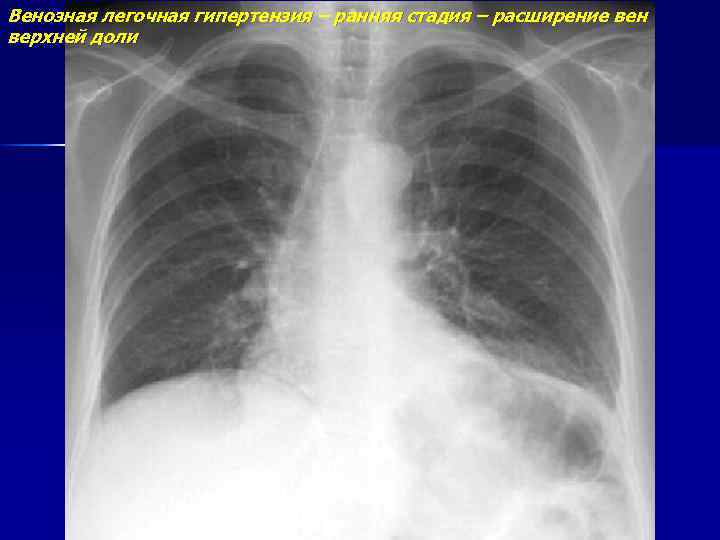

Венозная легочная гипертензия – ранняя стадия – расширение вен верхней доли